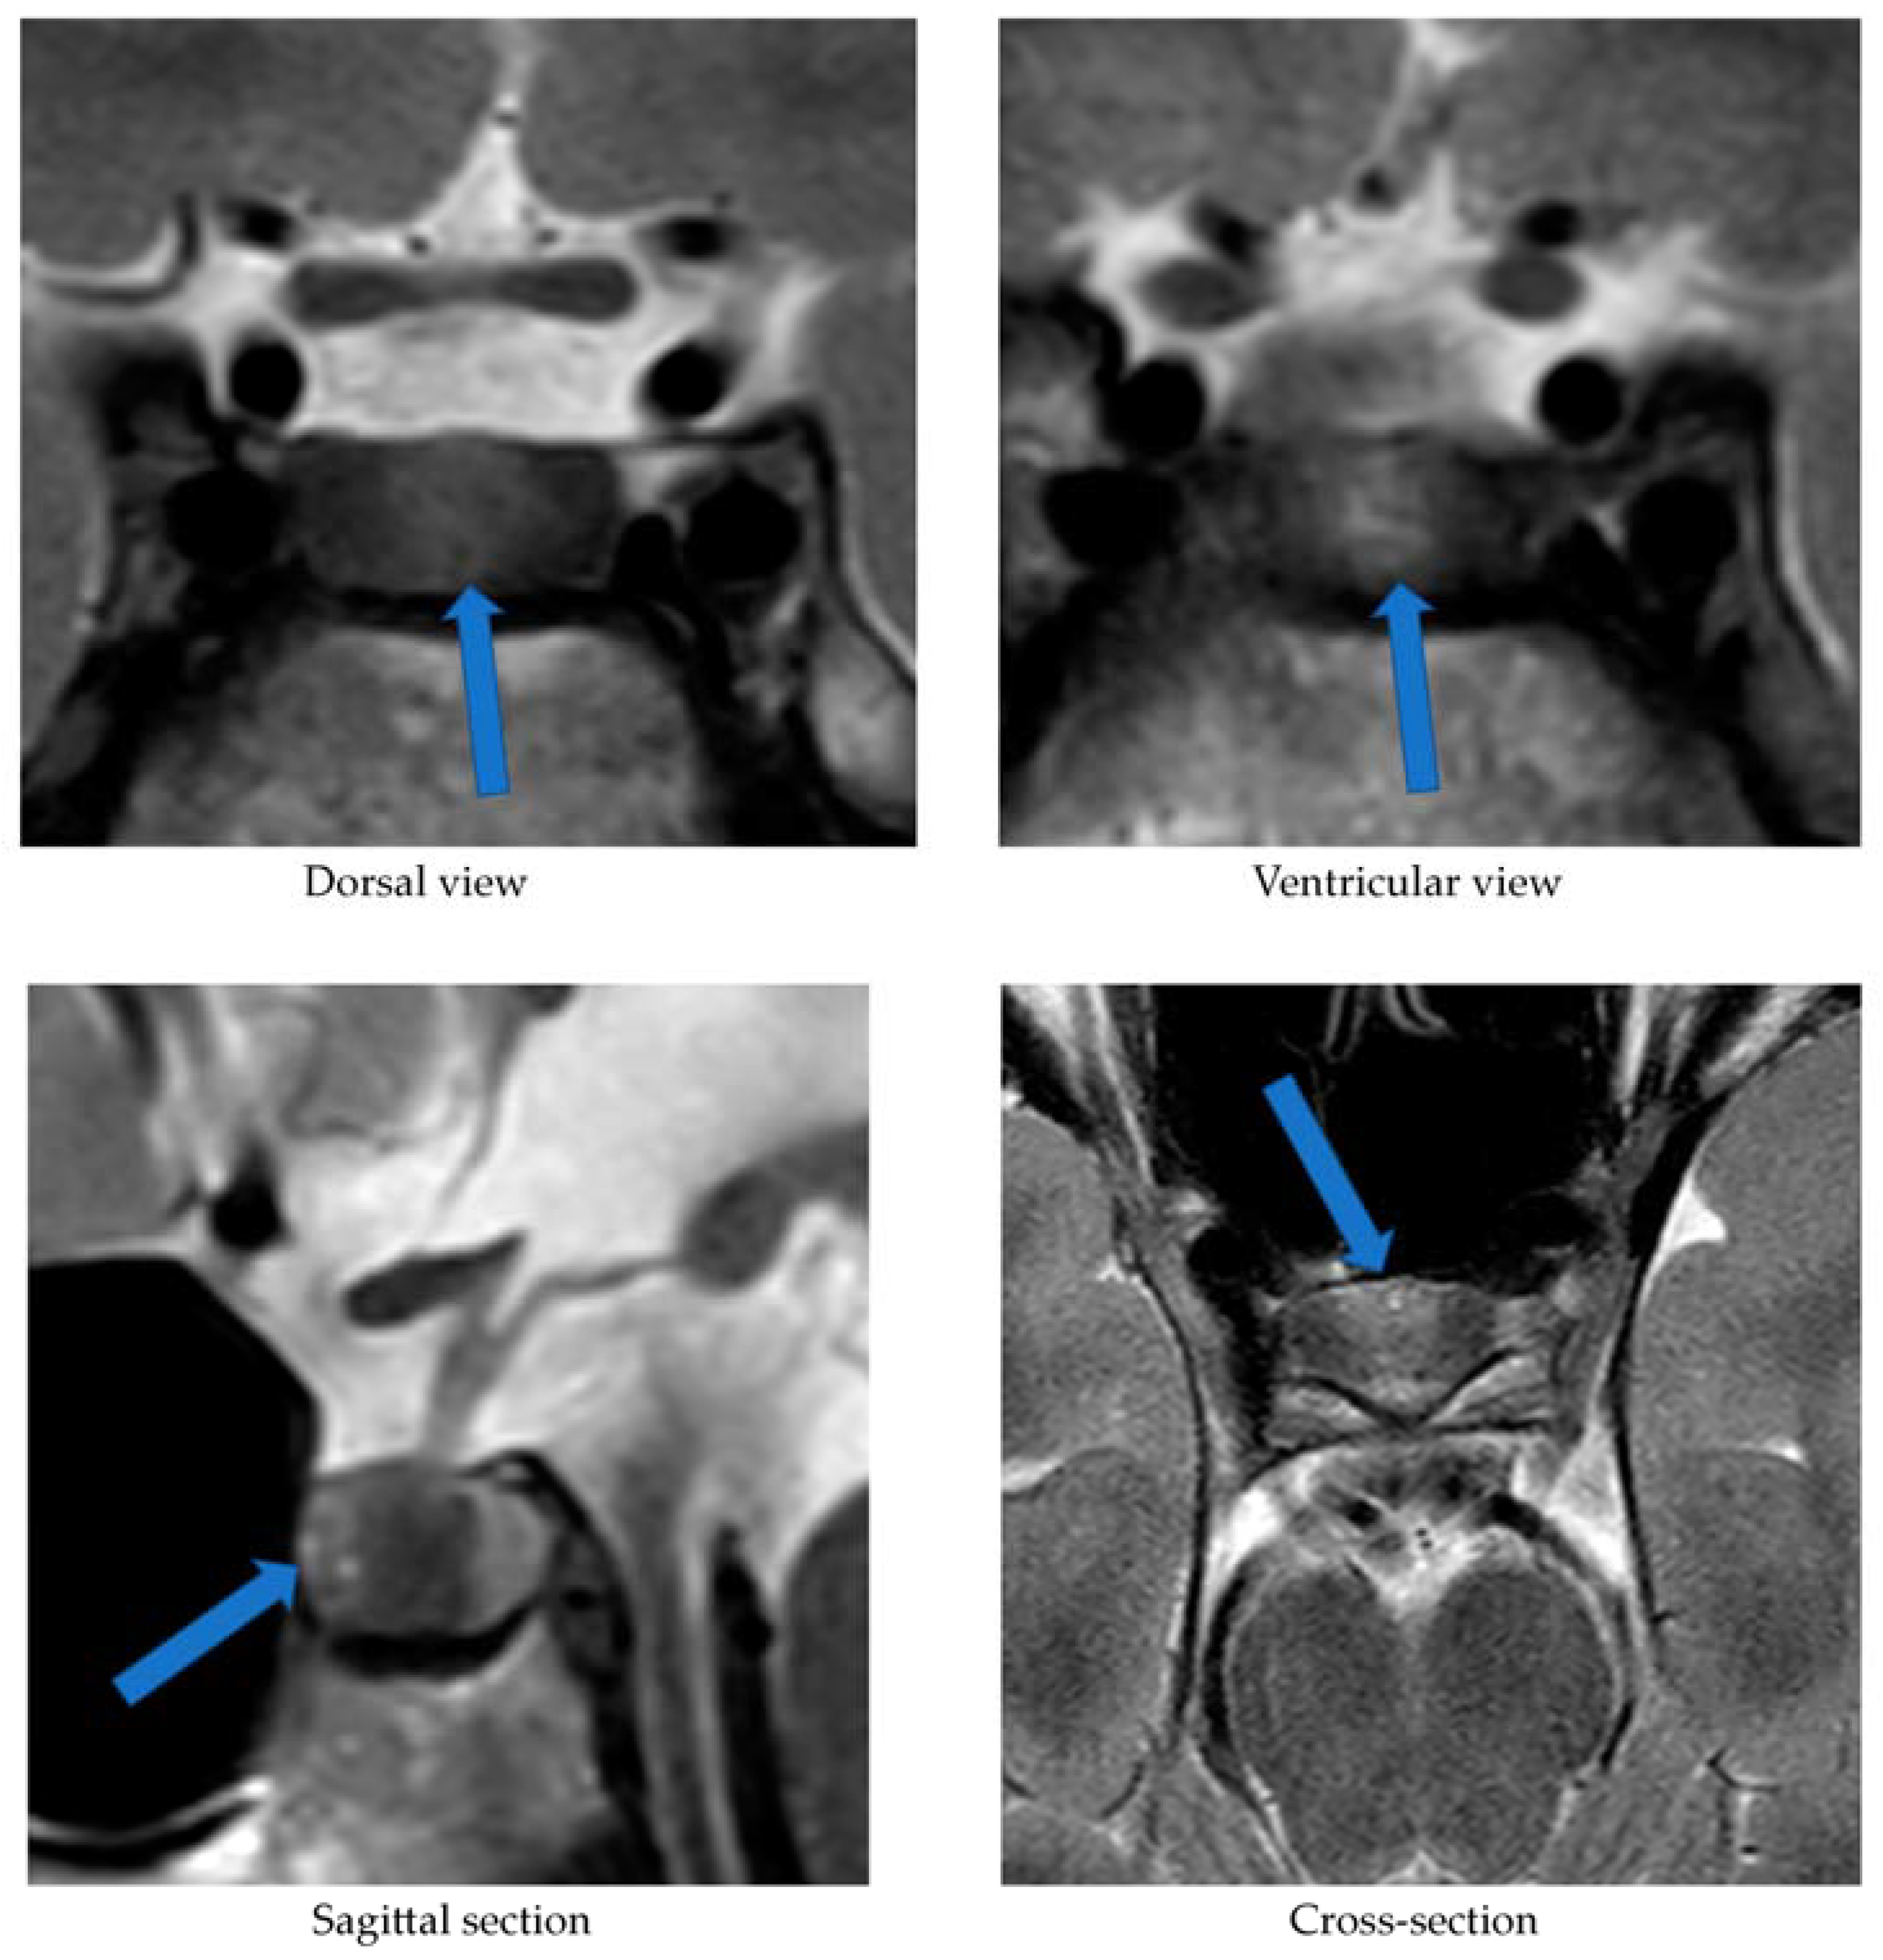

Alongside continued steroid therapy for autoimmune hepatitis, profiles of cortisol and ACTH secretion were performed. Due to the patient’s elevated cortisol levels during night hours (cortisol 24:00—10.7 µg/dL), an overnight dexamethasone suppression test (DST) and low-dose dexamethasone suppression test (LDDST) were performed. After administering 1 mg dexamethasone (23:00), his morning cortisol level (8:00) still remained elevated (cortisol—3.4 µg/dL). However, after administering 0.5 mg dexamethasone every 6 h for the next 2 days, cortisol levels (8:00) normalized (cortisol—1.0 µg/dL). An MRI of the pituitary gland showed only a poorly demarcated area in the anterior part of the glandular lobe, measuring approximately 2.0 × 3.5 × 5.0 mm on T2W images (Figure 3). A follow-up MRI examination was recommended, which was performed during the child’s next hospitalization in January 2022. The previously described area was still very faint.

Our patient’s case also demonstrates that MRI is not a perfect method of visualizing an ACTH-secreting pituitary adenoma. In the first MRI examination performed upon our patient, a poorly demarcated area (2.0 × 3.5 × 5.0 mm) was described in the anterior part of the glandular lobe; in the examination performed 6 months later, this area maintained poor visibility, while laboratory results at the time clearly indicated an ACTH-dependent form of CS. It was only the bilateral inferior petrosal sinus sampling (BIPSS) that allowed a clear diagnosis. Data from the literature indicate that microadenomas smaller than 3–4 mm are visible on MRI in only half of cases. In two large studies including children, pituitary adenomas were found on MRI in 63% and 55% of cases [18]. Among the patients with CD studied by Wędrychowicz et al. [3], pituitary adenomas were described on MRI in all of them, but in two patients (50%) this was only achieved upon follow-up. In the standard procedure, in the absence of a pituitary lesion in the MRI examination, it is recommended that a BIPSS be performed. In the case of our patient, this examination was necessary to make a definitive diagnosis.

Figure 3. MRI examination image depicting the poorly demarcated area in the anterior part of the glandular lobe. The arrows point to a structure suspected of being an adenoma.